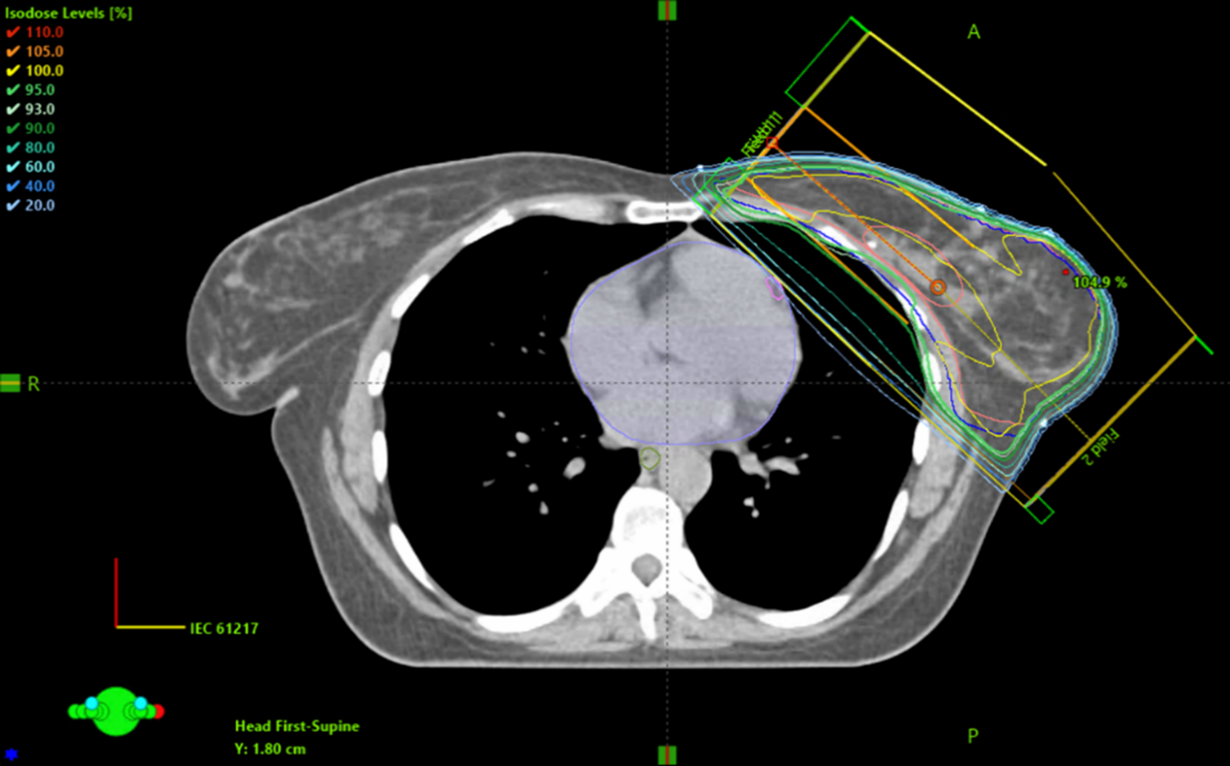

Figur 6. Exempel på dosplan med tangentiella strålfält.

Figur 7. Exempel på BEV för ett tangentiellt strålfält.

Konventionella planer mot bröst eller bröstkorgsvägg och regionala lymfkörtlar

Figur 8. Exempel som visar placeringen av isocenter och CT-snittet för övergången mellan tangentiella strålfält över brösttarget och strålfälten över körteltarget.

Figur 9. Exempel på BEV för strålfält över körtelvolymen.

Figur 10. Exempel på dosplan med strålfält över bröstkörtelvolymen.

Figur 11. Exempel på BEV för tangentiella fält vid behandling med körtlar.